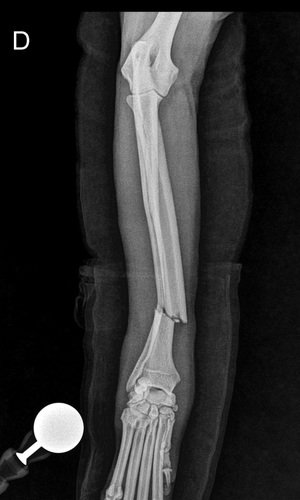

- Linhas de fraturas oblíquas e completas em diáfise distal de rádio e ulna direitos, com leve desvio do eixo ósseo.

- Aumento do volume de tecidos moles adjacentes ao foco de fraturas.

- Articulações umerorradioulnar e radiocárpica com relação preservada. Superfícies articulares lisas e regulares.

- Áreas de inserções tendíneas dentro da normalidade.

Impressão diagnóstica:

- Fraturas de rádio e ulna direitos, associado a edema dos tecidos adjacentes.

Encaminho paciente supracitado para realização de osteossíntese de rádio e una direita

Paciente adotado claudicando de membro torácico direito.

Com instabilidade de rádio e ulna. Radiografia confirmou fratura oblíqua curta de rádio direito